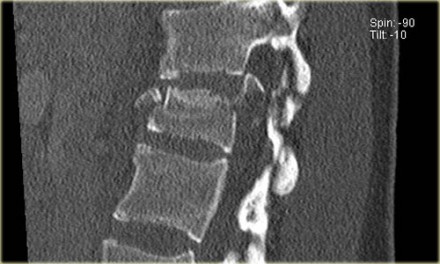

The images are of a patient with a typical bamboo spine as a result of ankylosing spondylitis.

After a fall on his back no fracture was seen on the x-rays.

However the CT shows a thin fracture line through the anterior side of the vertebral body and also through the spinous process.

Continue with the MR-images.